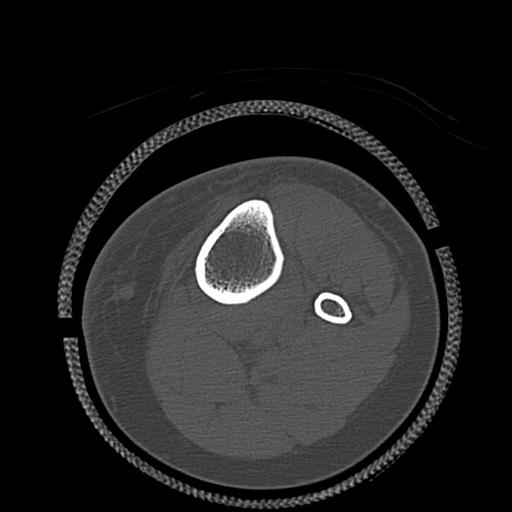

102803 1/12(キウスなし) 1/27 左下腿 4R 30歳女性 左脛骨軸内釘